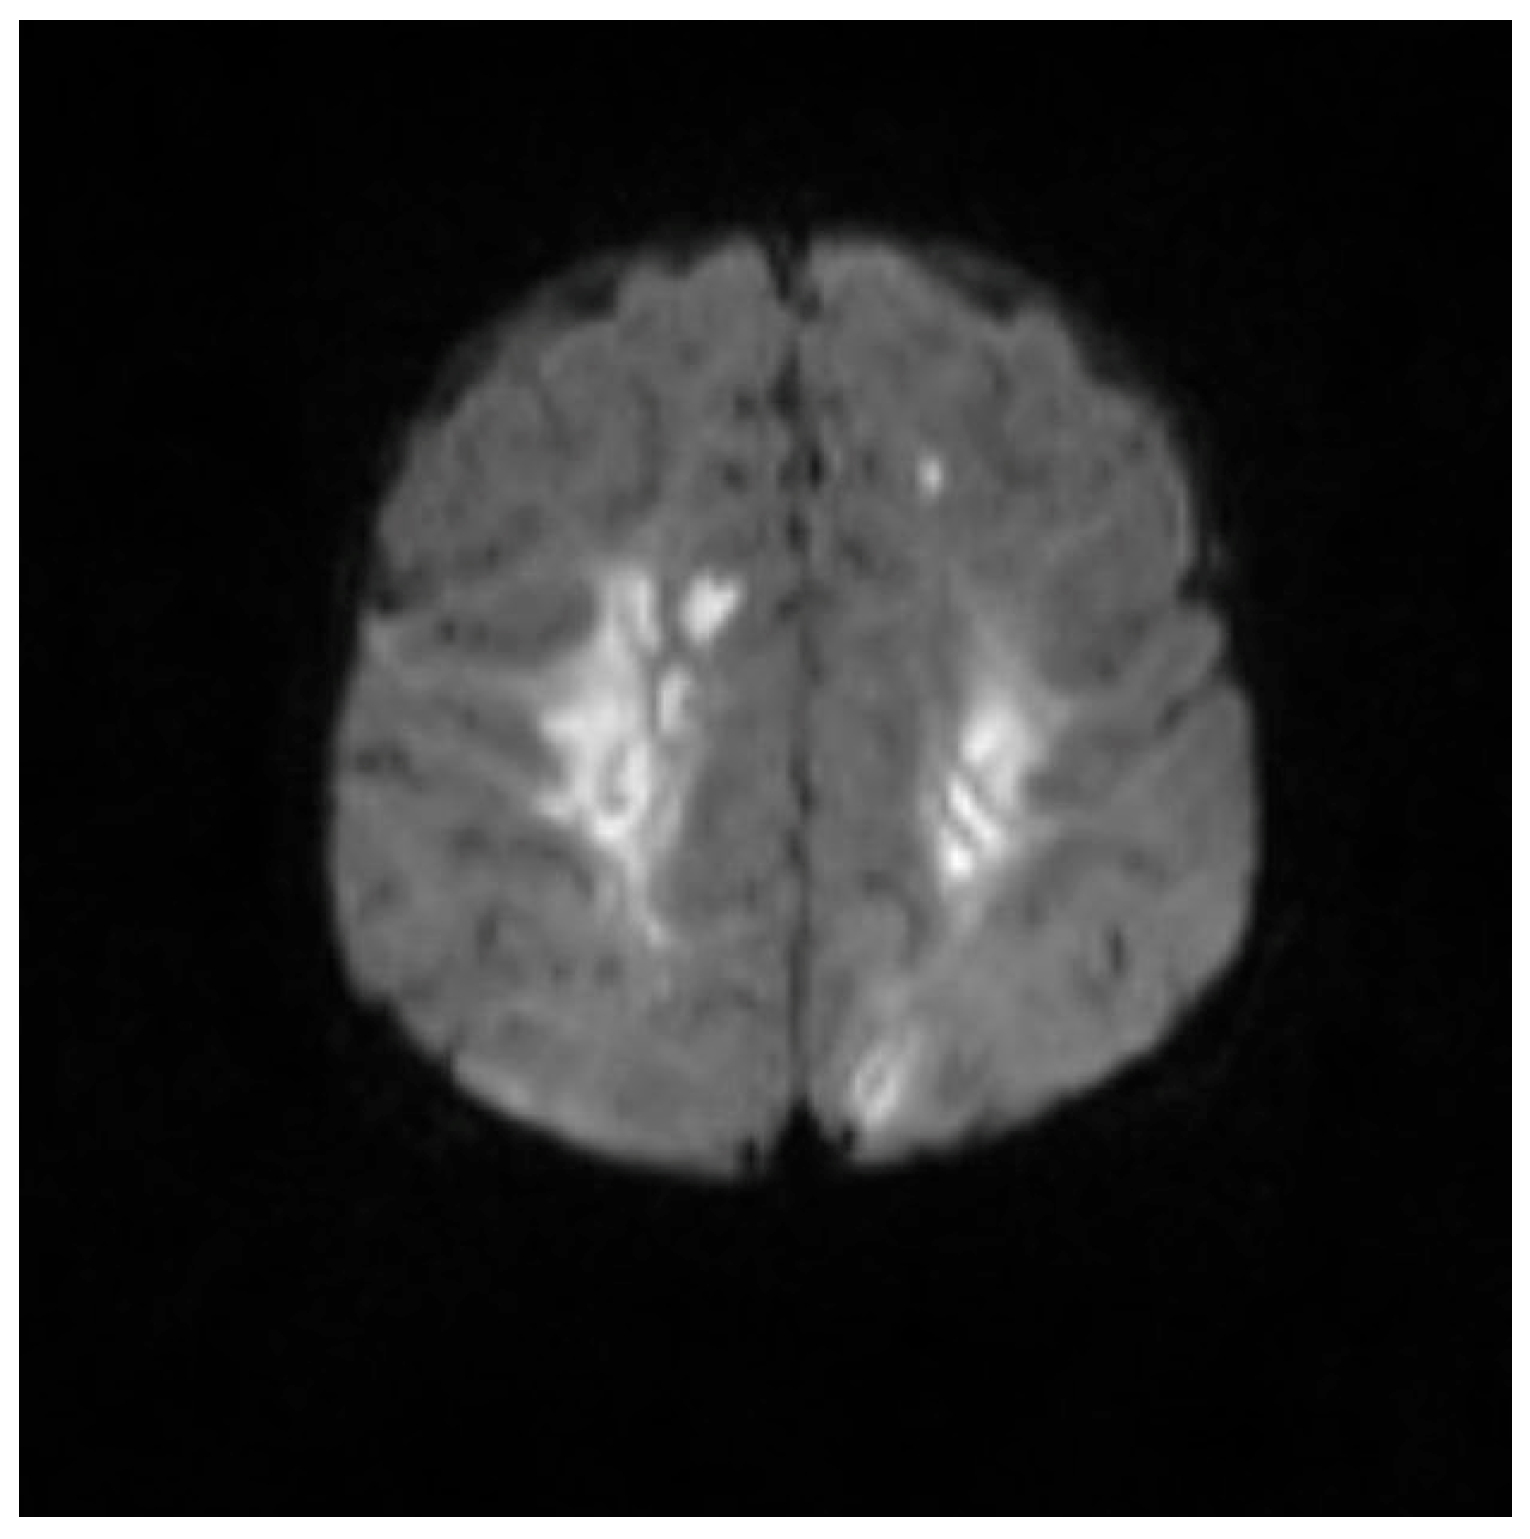

An MRI repeated on 11 November 2022, after 7 weeks of treatment, showed interval resolution of the abscesses and subdural empyema, with resolution of leptomeningeal disease. Expected changes were observed, including brain volume loss and periventricular leukomalacia, with the previously described foci of enhancement. The internal auditory canals appeared unremarkable (Figure 1, Figure 2, Figure 3, Figure 4 and Figure 5).

Figure 5. MRI brain scan showing periventricular lesions.